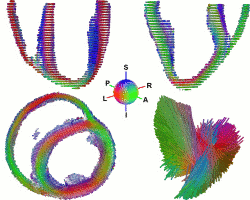

A Statistical Study of the Cardiac Diffusion Tensor Images

While the main geometrical arrangement of myofibers has been known for decades, its variability between subjects and species still remains largely unknown. Understanding this variability is not only important for a better description of physiological principles but also for the planning of patient-specific cardiac therapies. Furthermore, the knowledge of the relation between the myocardium shape and its myofiber structure is an important and required stage towards the construction of computational models of the heart since the fiber orientation plays a key role when simulating the electrical and mechanical function of the heart. The knowledge about fibre orientation has been recently eased with the use of Diffusion Tensor Imaging (DTI) since there is a correlation between the myocardium fibre structure and diffusion tensors. DTI also has the advantage to provide directly this information in 3D with a high resolution, unfortunately it is not available in vivo due to the cardiac motion. A statistical study of ex vivo cardiac DTI will help in understanding the cardiac fibre structure and in modeling the electromechanical behavior of the heart.

While the main geometrical arrangement of myofibers has been known for decades, its variability between subjects and species still remains largely unknown. Understanding this variability is not only important for a better description of physiological principles but also for the planning of patient-specific cardiac therapies. Furthermore, the knowledge of the relation between the myocardium shape and its myofiber structure is an important and required stage towards the construction of computational models of the heart since the fiber orientation plays a key role when simulating the electrical and mechanical function of the heart. The knowledge about fibre orientation has been recently eased with the use of Diffusion Tensor Imaging (DTI) since there is a correlation between the myocardium fibre structure and diffusion tensors. DTI also has the advantage to provide directly this information in 3D with a high resolution, unfortunately it is not available in vivo due to the cardiac motion. A statistical study of ex vivo cardiac DTI will help in understanding the cardiac fibre structure and in modeling the electromechanical behavior of the heart.

Tensor computing

The emergence of diffusion tensor imaging (DTI) in the medical imaging community led to challenges in mathematics in order to manipulate 2nd order symmetric positive-defined matrices, so called tensors. In DT-MRI, each voxel of the brain contains a tensor, which is the 2nd order approximation of the brownian motion of water at this specific location. As water tends to move along oriented tissues (such as white matter neural fibers) diffusion tensors are likely to be aligned with the underlying structures. Due to the noise corrupting the data, the tensor field needs adequate post-processing before any further analysis. However, one cannot manipulate tensors like scalars (the tensor space is not a vector space). We used results in differential geometry to manipulate tensors while ensuring to remain on the tensor space, i.e. to keep the positive-defined constrain verified at all time. Applications are: tensor field regularization (PDE, etc.) and shape statistics (see the collaboration Epidaure-LONI).

The emergence of diffusion tensor imaging (DTI) in the medical imaging community led to challenges in mathematics in order to manipulate 2nd order symmetric positive-defined matrices, so called tensors. In DT-MRI, each voxel of the brain contains a tensor, which is the 2nd order approximation of the brownian motion of water at this specific location. As water tends to move along oriented tissues (such as white matter neural fibers) diffusion tensors are likely to be aligned with the underlying structures. Due to the noise corrupting the data, the tensor field needs adequate post-processing before any further analysis. However, one cannot manipulate tensors like scalars (the tensor space is not a vector space). We used results in differential geometry to manipulate tensors while ensuring to remain on the tensor space, i.e. to keep the positive-defined constrain verified at all time. Applications are: tensor field regularization (PDE, etc.) and shape statistics (see the collaboration Epidaure-LONI).